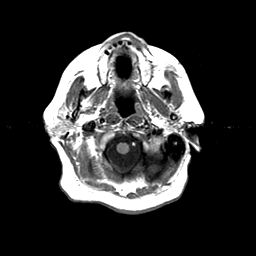

Basal Ganglia Calcification: T1-weighted MR -- Slice #1

[Home][Help][Clinical] Slice 1